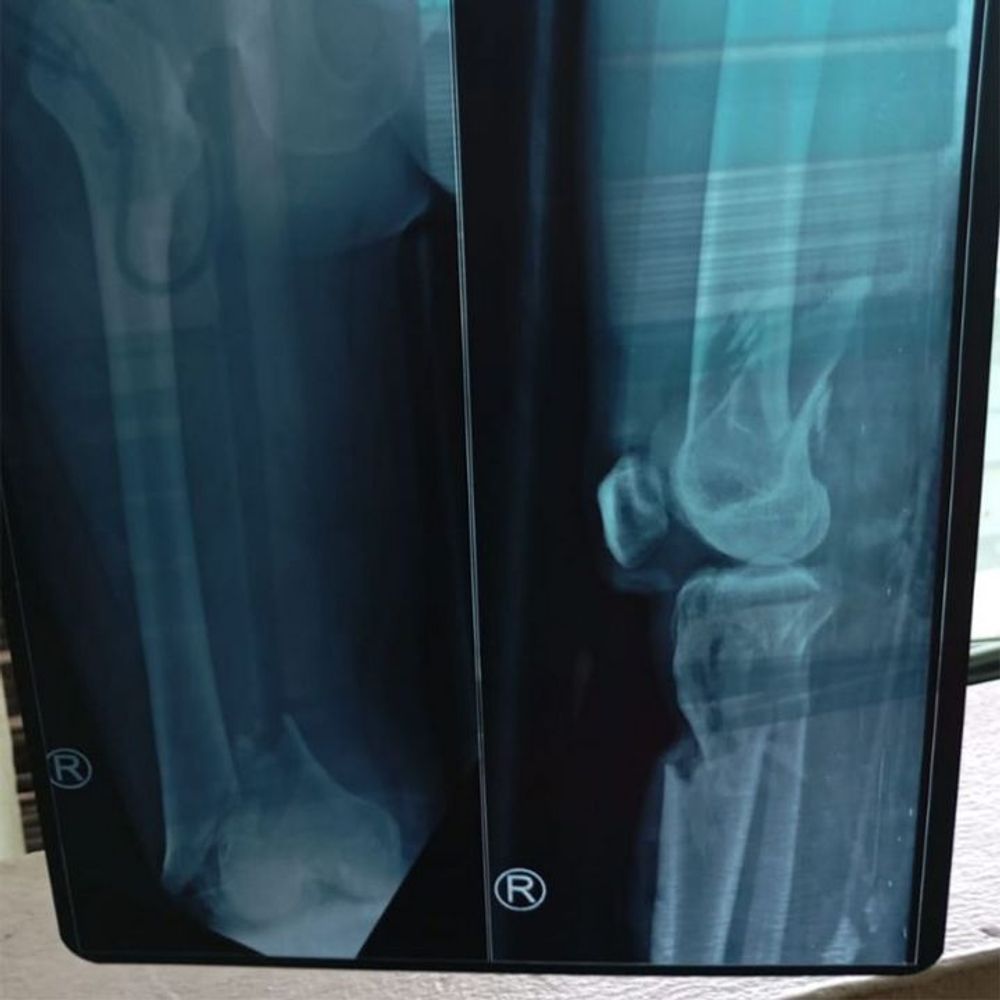

The devastating news reached his heavily pregnant wife—Pak Anjar lay unconscious in the ER, covered in blood after being hit by a reckless driver. Both of his legs were severely damaged—bones, nerves, and blood vessels completely shattered beyond repair. His only chance of survival is an amputation to prevent further complications from spreading to his vital organs. But how can they afford it? His daily wage as a laborer barely covers their basic needs, and now he’s supposed to welcome his first child…

Doctors confirmed the worst—his legs couldn’t be saved. The only way to keep him alive was an urgent amputation. With no other option, Pak Anjar and his wife had to accept this heartbreaking reality. But the hospital bills were beyond their means.